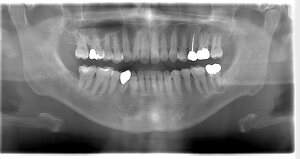

インプラント治療の症例1

レントゲン写真

- 透過像

| 年齢 | 50代・男性 |

|---|---|

| 主訴 | 右下歯が疼く |

| 治療内容 | ・右下6番インプラント ※1:FGG(遊離歯肉移植術)とは、足りない歯ぐきを上顎から上皮を切り取り移植する外科手術 |

| 治療費 | 合計:902,000円(税込) ■内訳 |

| 治療期間 | 9ヵ月 |

| 治療方針 | 右下の当該歯は歯根破折により保存不可能と診断しました。歯周疾患も伴っていたため抜歯後に骨吸収※1が大きく起こることが予測できました。チタンメッシュ併用骨再生誘導法(GBR※2)を選択しインプラント埋入と同時に行い自然な歯槽骨のラインを再現しました。またGBRを行う際にインプラント辺縁の付着歯肉の減少が起こる為、遊離歯肉移植術(FGG※3)を行い清掃性を考慮した形態に仕上げました。 ■治療方針の解説 治療した右下の歯をレントゲンで撮影したところ根本の部分に黒く写る箇所があり「根尖性慢性周囲炎※1」と診断。また歯周病も進行していました。 ※1 骨吸収・・・歯槽骨という歯を支える骨がなくなっていくこと |

| 担当者所見 | 主訴の右下だけでなく歯茎の腫れ、発赤があり不良補綴や不良充填など他にも治療箇所が多数ありました。プラークコントロールが不良であった為まずはブラッシング指導を行いセルフケアの重要性を理解していただくところからスタートしました。 右下6番の歯はインプラント治療を行なった結果審美的にも機能的にも患者様の満足を得ることができました。骨造成と歯肉移植も行なった為インプラントを支える十分な歯周組織の獲得ができたと思っております。 |